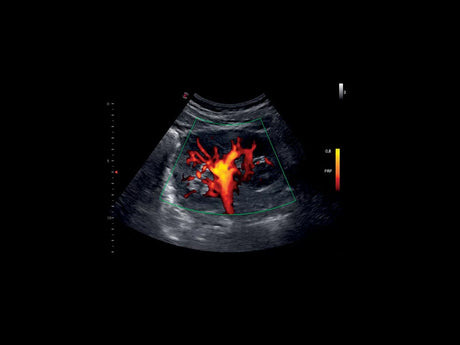

La qualité d’image est au cœur de la philosophie Esaote. Grâce à ses sondes de dernière génération et à son traitement du signal avancé, la marque permet une visualisation fine des structures anatomiques, même les plus profondes. Leurs échographes intègrent des écrans tactiles haute résolution, une interface claire et une connectivité complète, favorisant un flux de travail rapide et efficace.

Les échographes Esaote offrent une restitution d’image d’une grande précision, permettant un diagnostic fiable dans toutes les spécialités. Le traitement numérique optimise le contraste et la netteté, réduisant les artefacts et améliorant la détection des tissus pathologiques. Ces performances sont particulièrement appréciées en gynécologie, où la lisibilité des structures pelviennes ou obstétricales est déterminante.